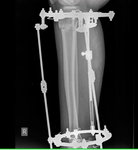

Рентген в 90дней.

IMG_1444-25-02-19-05-32.JPG

IMG_1443-25-02-19-05-32.JPG